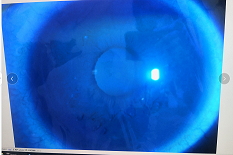

圓錐角膜要做那種治療比較好

【文章導(dǎo)讀】圓錐角膜的治療應(yīng)該依據(jù)角膜發(fā)展的時(shí)期選擇。目前圓錐角膜按照臨床癥狀大致可以分為四個(gè)時(shí)期,分別為潛伏期、初發(fā)期、完成期和瘢痕期,各個(gè)時(shí)期的主要癥狀表現(xiàn)如下: 潛伏期:

圓錐角膜的治療應(yīng)該依據(jù)角膜發(fā)展的時(shí)期選擇。目前圓錐角膜按照臨床癥狀大致可以分為四個(gè)時(shí)期,分別為潛伏期、初發(fā)期、完成期和瘢痕期,各個(gè)時(shí)期的主要癥狀表現(xiàn)如下:

潛伏期:癥狀不明顯。

初發(fā)期:開始近視,同時(shí)散光和不規(guī)則散光度數(shù)也會(huì)逐漸增加。

完成期:發(fā)展迅速,角膜明顯前突,視力銳減。

瘢痕期:角膜急性角膜水腫、混濁,消退后基質(zhì)層殘留瘢痕。

對(duì)于對(duì)于進(jìn)展非常慢,可能幾年曲率都不變化的圓錐角膜,可以觀察隨診,或者佩戴RGP矯正。如果角膜發(fā)展較快,近視散光度數(shù)增加較快,則需要通過(guò)角膜交聯(lián)來(lái)治療。

圓錐角膜的形成機(jī)制就是膠原變薄,變?nèi)?。圓錐角膜患者的角膜膠原變薄了以后,彈性增加,正常的眼壓會(huì)使角膜向前膨隆。

角膜膠原交聯(lián)手術(shù)可以通過(guò)藥物,維生素B2和紫外線交聯(lián),使角膜里面的膠原纖維的硬度增加,在對(duì)抗正常眼壓情況下,對(duì)抗力增加。交聯(lián)后角膜的韌度增加,就不容易再往前繼續(xù)發(fā)展。

但如果已經(jīng)發(fā)展到圓錐后期,再去交聯(lián)就沒有意義,就只能通過(guò)角膜移植手術(shù)治療,把向前凸起的角膜給切掉,換成新的角膜。

目前圓錐角膜的治療方式主要就是配鏡矯正、角膜膠原交聯(lián)手術(shù)以及角膜移植手術(shù)這幾種。